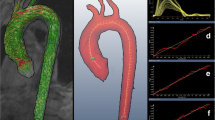

To estimate the 3D length of the aortic arch, the centers of the aortic lumen were first selected by an experienced user on each SSFP axial and coronal slices in a 3D Coordinate-System. Six to eight markers were defined for the ascending and the descending segment on axial slices, and three markers were defined for the top of the aortic arch on coronal slices. The 3D coordinates of the selected centers were computed from the DICOM headers of the MR images, and were interpolated with a 3D Bezier curve (Figure 1). The length of the 3D Bezier curve comprised between the ascending and descending aorta planes defined from the PC images was considered for the estimation of the AA_PWV.

The estimation of the aortic arch length and the transit time was repeated by two independent operators to assess inter-observers variability.

The aortic arch PWV (Arch_PWV) was estimated from the length of the aortic arch, and the temporal shift between the mean velocity waveforms in the ascending and descending aorta. In our study, a 3D approach was used to assess the aortic arch length from both the coronal and axial slices, rather than the traditional 2D measurement which is usually performed from a single sagittal oblique section by a manual selection of the centreline of the aorta [13, 15–17]. The advantage of our 3D technique is its ability to better take into account the 3D geometry of the aorta. Indeed, the curvature of the aortic arch is not always aligned in a specific plane regarding to the position of the ascending and descending aorta. Since our technique required a manual positioning of the centers of the aorta lumen on axial and coronal data acquired during two successive apneas, its reproducibility was studied, resulting in very low inter-observer variability. The transit time was estimated from the systolic up-slope portion of the velocity waves using an automated method based on a least squares minimization technique used in previous studies for the evaluation of the effect of coarctation repair [20] and aging [21] on CMR aortic stiffness indices. Other methods based on the foot-to-foot [18] or on the cross-correlation [32] were used to estimate the transit time. Similar to the foot-to-foot approaches, the systolic up-slope was considered in our method rather than the entire curve as proposed in the cross-correlation methods. This choice was based on the unidirectional and reflectionless nature of the systolic up-slope [16, 26] and aimed at minimizing the influence of the morphology of the downslope which may be altered by aortic stiffening and disorganization of the flow during end systole.